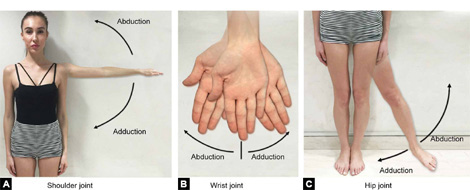

Abduction (Figs. 1.5A to C)—Movement of limb away from mid-sagittal plane of body.

Adduction (Figs. 1.5A to C)—Movement of limb towards the mid-sagittal plane of body.

(Abduction and adduction movement occurs in coronal plane)